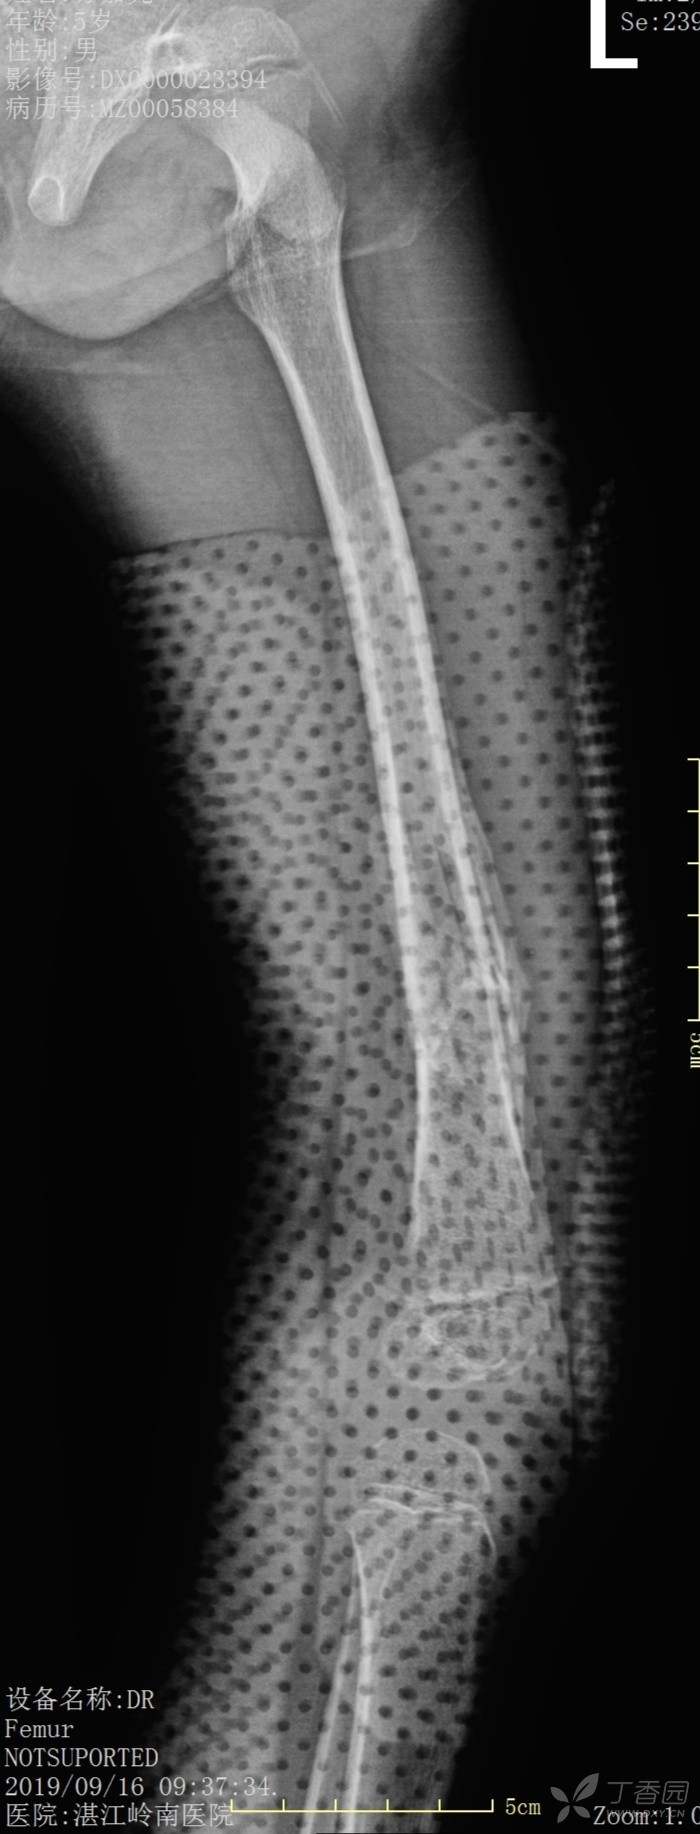

4岁患儿股骨骨折保守治疗一例

外伤时,保守1个月、2个月、6个月